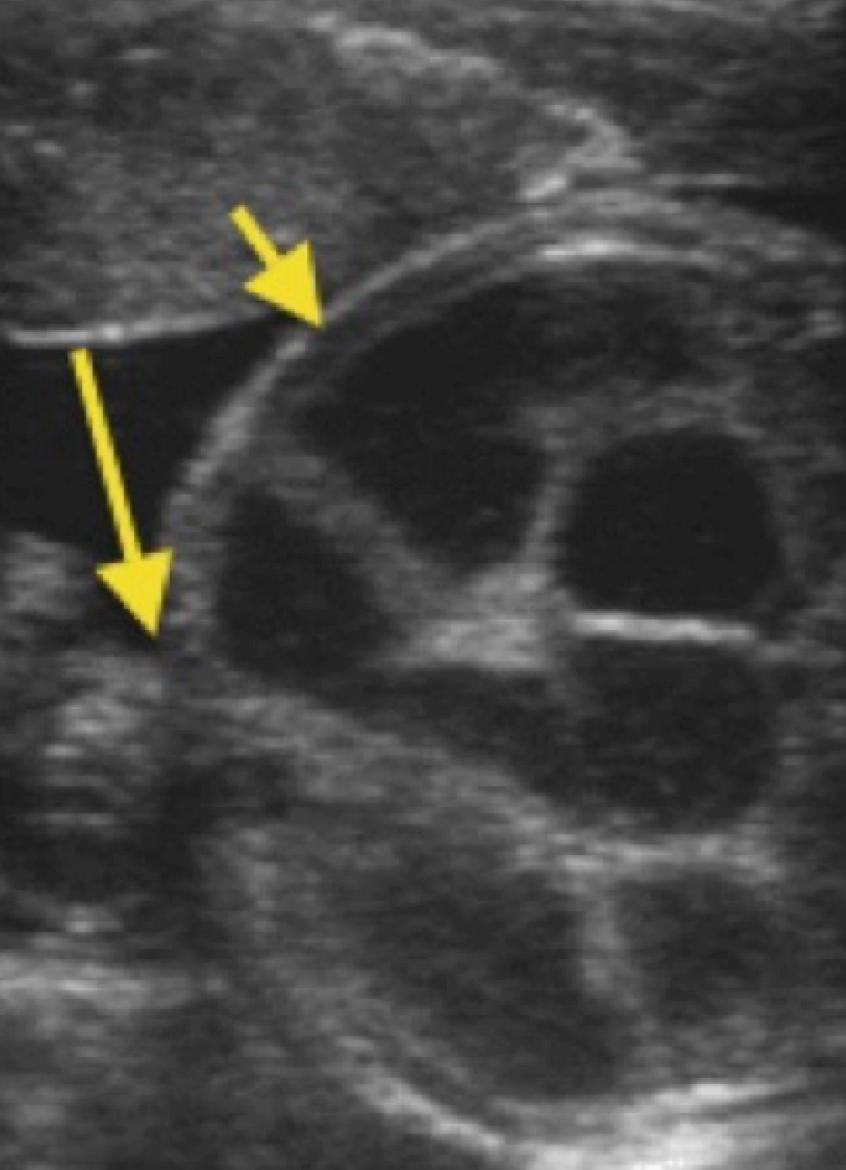

from radiopaedia.org

Gastroschisis Image